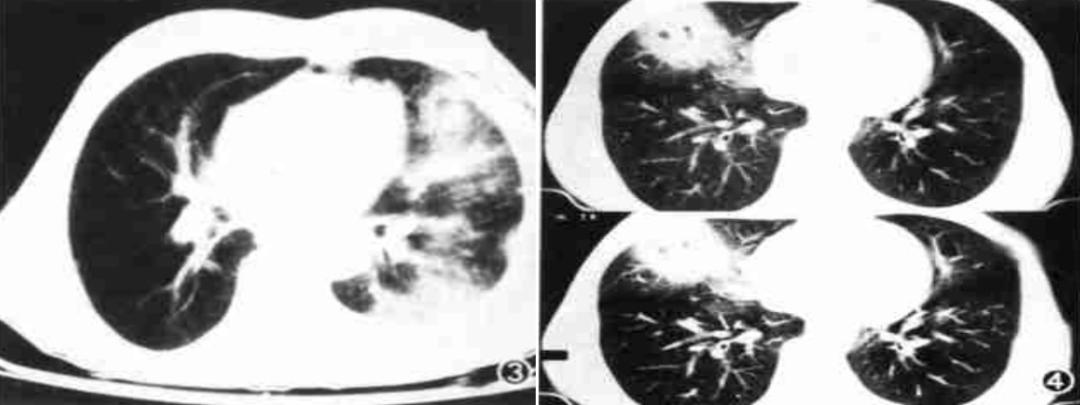

其影像学特点包括(图13):

(1)胸膜改变(早期即可出现):①胸膜斑:双侧胸壁中、下部对称性三角形阴影,部分有钙化;②胸膜增厚、粘连;③渗出性胸腔积液:双侧多见,可为血性。(2)肺部改变:①网状阴影(主要改变):中下肺细网、粗网、蜂窝状改变;②融合灶:双肺基底部,边界不清,范围不大的片状阴影;③肺门结构紊乱,密度增高,但无肺门淋巴结肿大。

图13:石绵肺的典型影像学表现(资料)